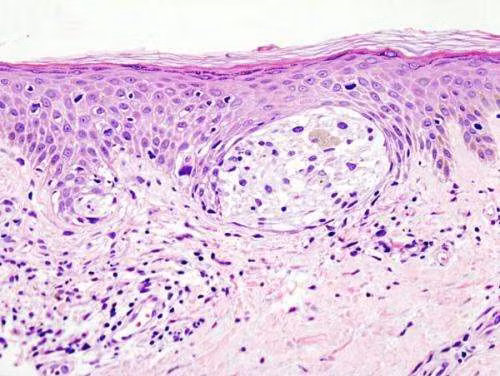

| Hình ảnh khối ung thư sinh thiết dưới da. |